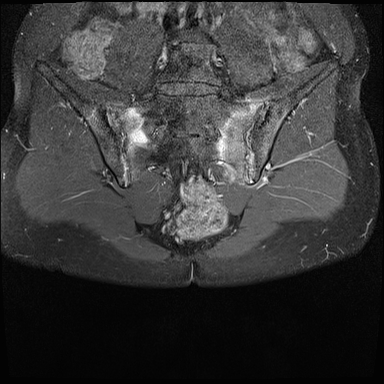

MRI

MRI chuỗi xung T1W sau tiêm thuốc tương phản từ của cùng bệnh nhân cho thấy bờ khớp cùng chậu không đều do bào mòn.

Có ngấm thuốc ở xương dưới sụn và phù nề tủy xương.

Không có tràn dịch khớp.

Thuốc tương phản từ tiêm tĩnh mạch không nhất thiết phải sử dụng để chẩn đoán viêm khớp cùng chậu.

Cuộn qua các hình ảnh MRI và so sánh với các dấu hiệu trên X-quang (hình ảnh cuối cùng).

Viêm khớp cùng chậu giai đoạn muộn với dính khớp cùng chậu.